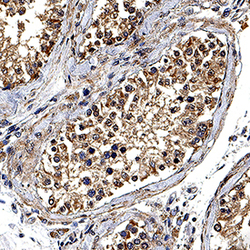

MAB9657-100 IHC

Full details

Method: Other validation